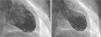

Caso clínicoUma doente de 54 anos com antecedentes de dislipidemia e hábitos tabágicos recorreu ao serviço de urgência (SU) por precordialgia opressiva, com irradiação dorsal. A dor teve início súbito em repouso 16 horas antes. Não tinha outros sintomas nem tinha estado sob eventos de stress nesse dia nem no passado recente. À chegada ao SU estava febril (38°C), mas os restantes sinais vitais e exame objetivo eram normais. O eletrocardiograma (ECG) apresentava apenas um padrão rS em DIII e aVF. O primeiro ecocardiograma efetuado no SU revelou dilatação ventricular esquerda com acinesia mesoapical de todas as paredes e hipercinesia de todos os segmentos basais, a condicionar imagem de balonização do ventrículo. A doente foi imediatamente enviada para o laboratório de hemodinâmica e submetida a cateterismo emergente. A ventriculografia revelou os mesmos achados previamente objetivados no ecocardiograma (Figura 1). A coronariografia revelou uma lesão suboclusiva mesodistal da artéria coronária obtusa marginal (Figura 2). Observaram‐se ainda irregularidades na artéria coronária direita.